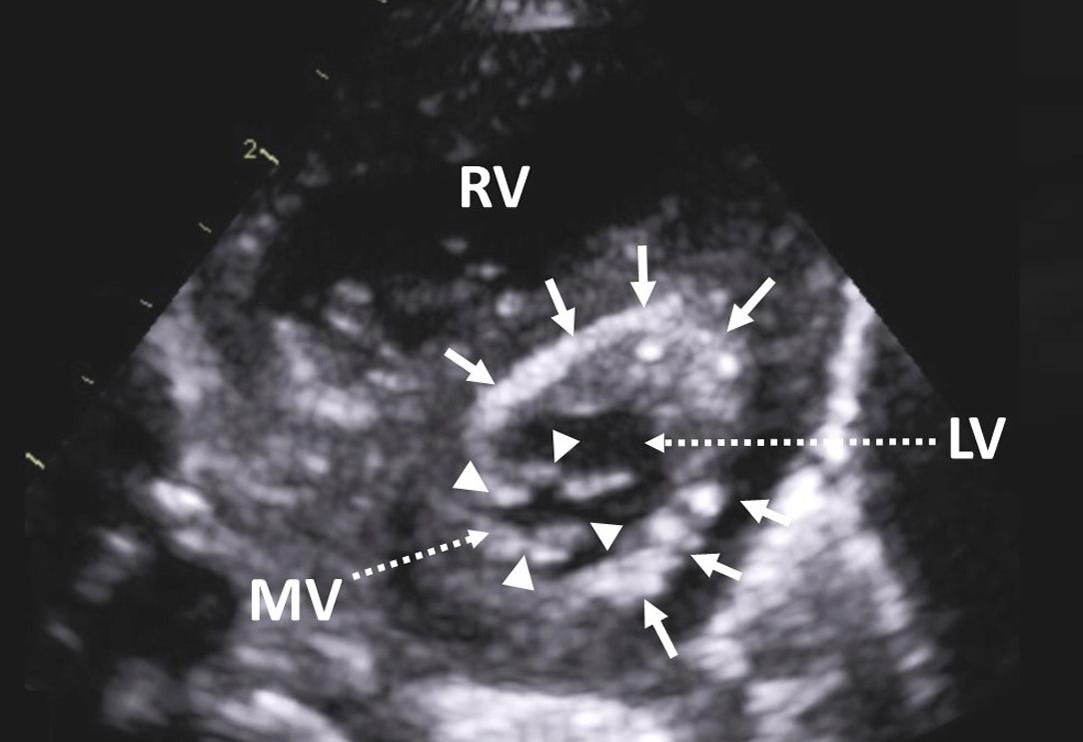

Figure 2, Parasternal short-axis view in a patient with hypoplastic left heart syndrome demonstrating a severely reduced mitral valve orifice area ( arrowheads ) and endocardial fibroelastosis ( arrows ). LV , left ventricle; MV , mitral valve; RV , right ventricle.